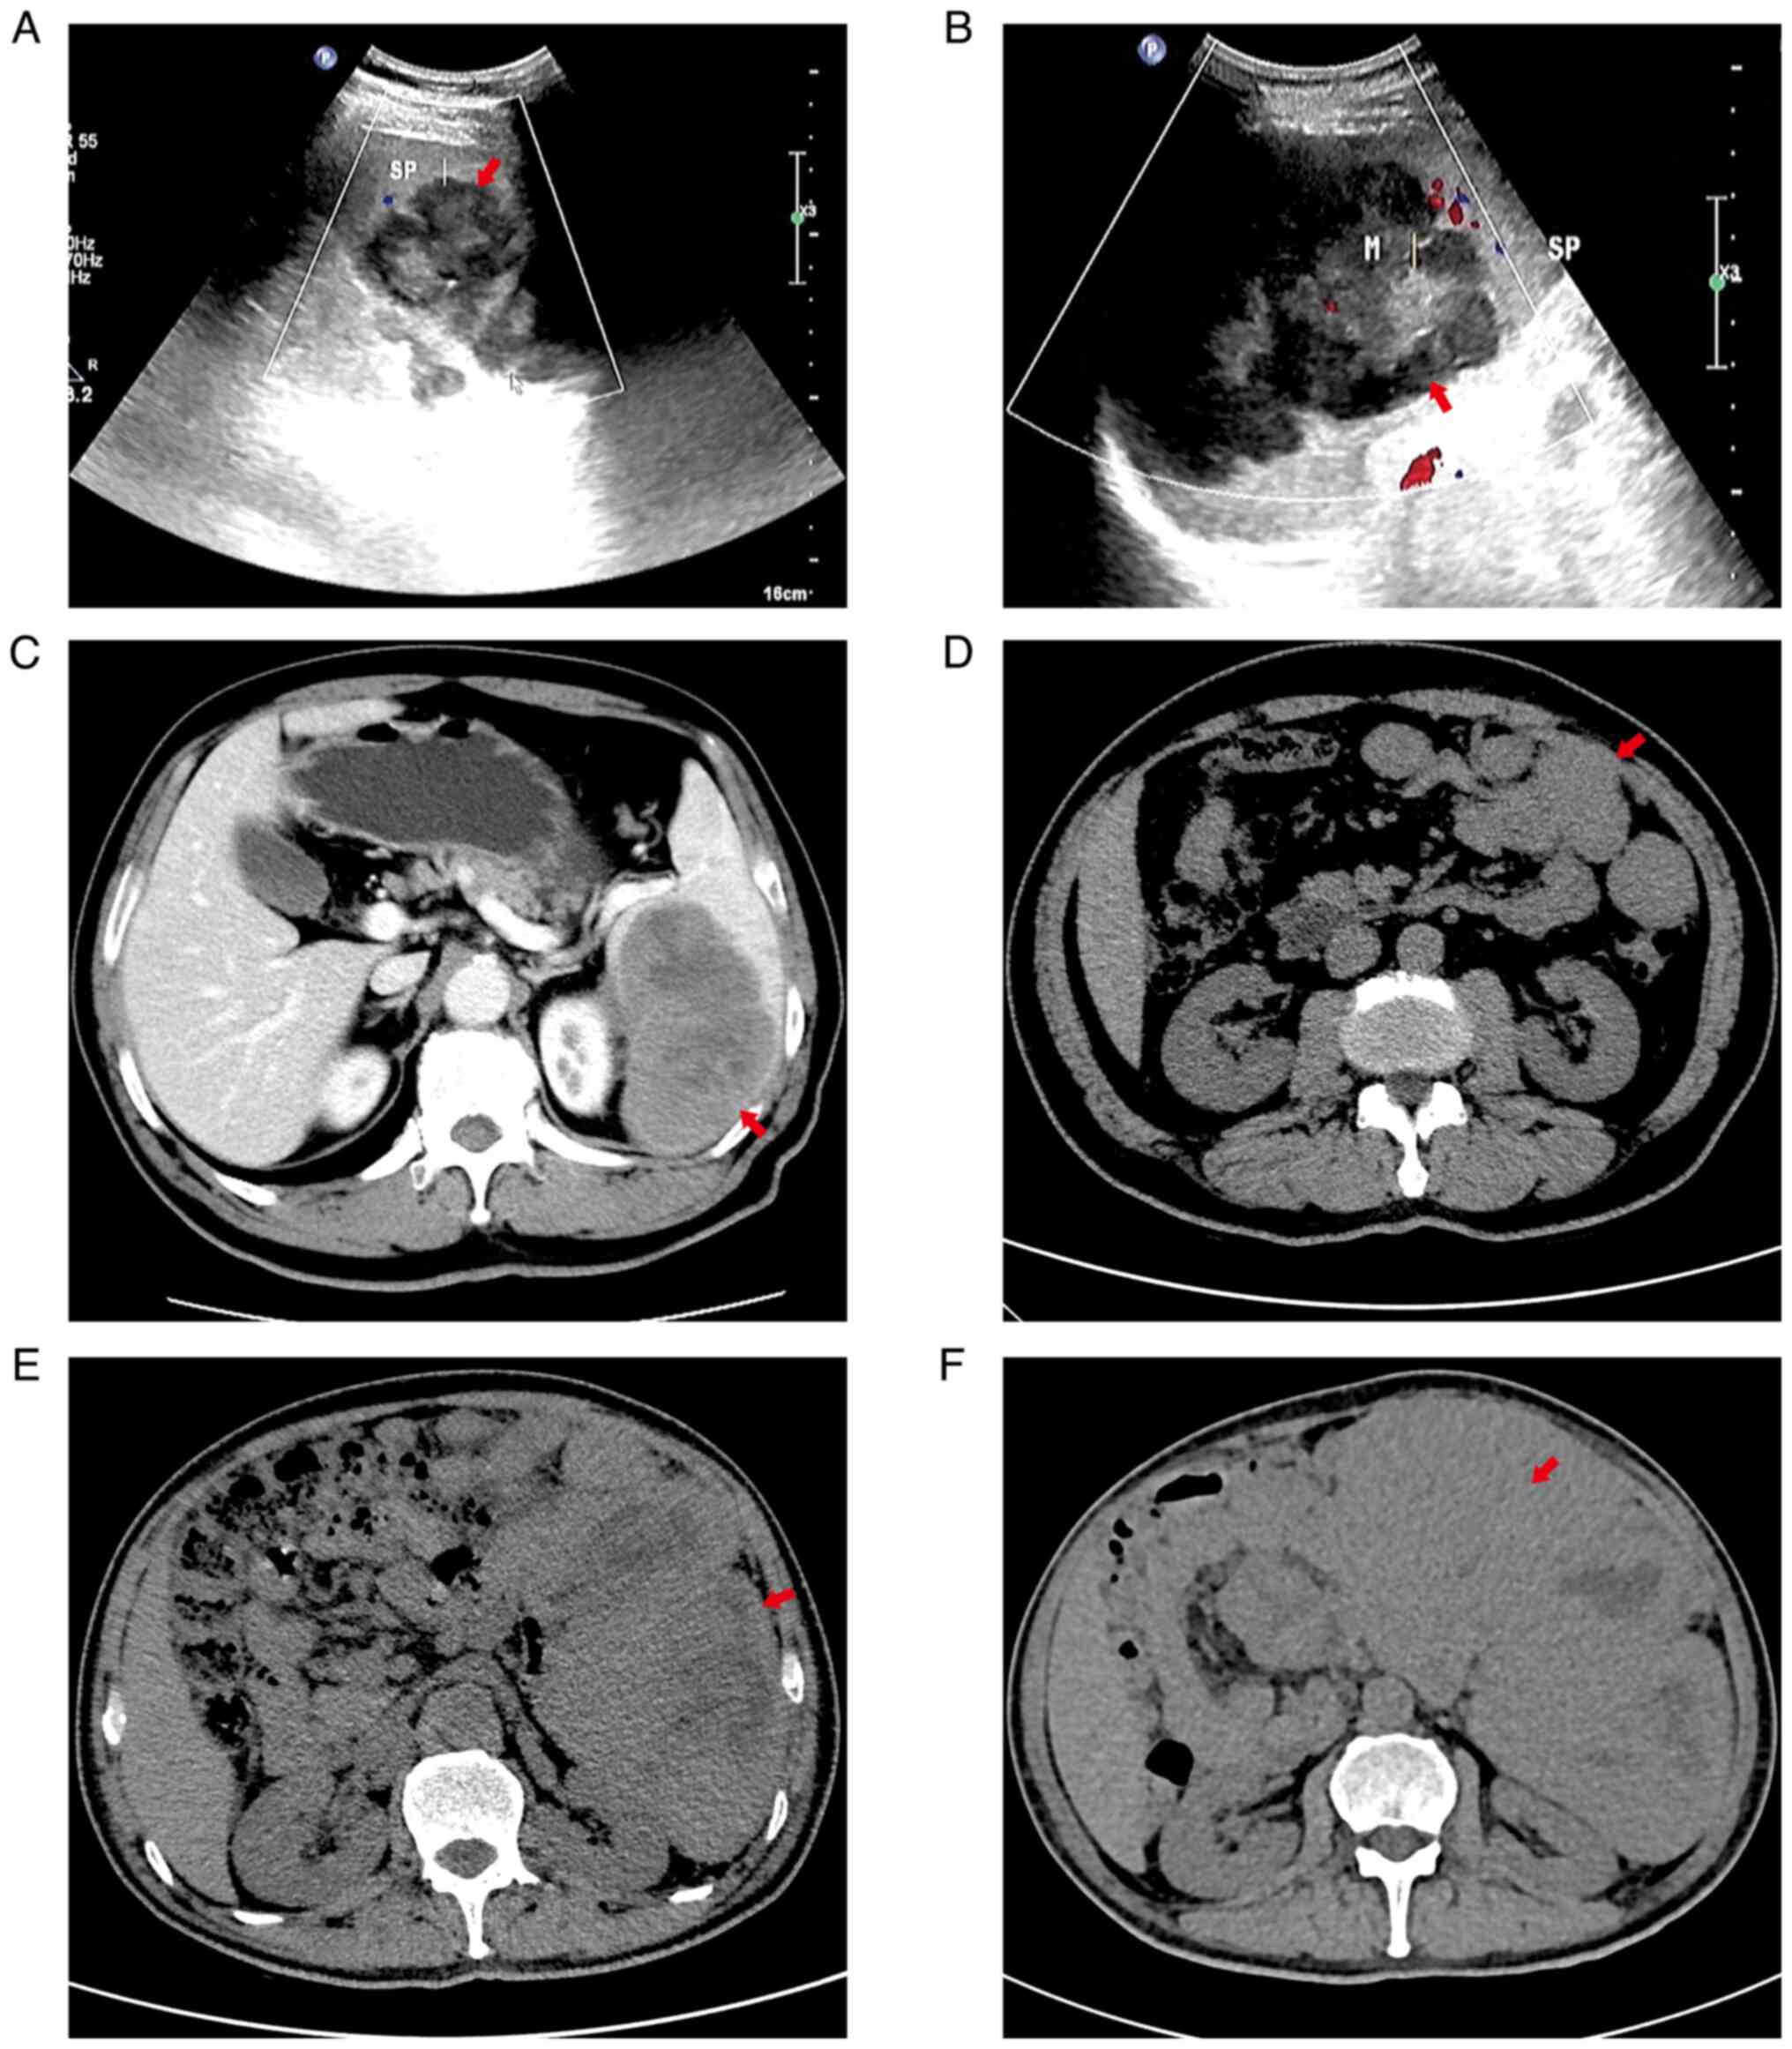

In November 2020, a male patient came to the First People's Hospital of Guangyuan (Guangyuan, China) for routine physical examination and a spleen mass was identified. There were no obvious symptoms at that time. Ultrasound and computed tomography images of the patient are provided in Fig. 1. At the first presentation, ultrasound examination with a Mindray M9 (Shenzhen Mindray Biomedical Electronics Co., Ltd; two-dimensional; Colo Flow; model of ultrasonic probe, C5-1S, 8 Hz) indicated that the dimensions of the tumor were 4.5×7.5 cm (Fig. 1A) and the patient did not undergo any immediate surgical treatment, as there was no discomfort. The patient was hospitalized at the First People's Hospital of Guangyuan due to left abdominal pain (Guangyuan, China) 74 days after the first presentation. Ultrasound indicated a tumor mass in the spleen, which had grown, with a measured size of 10.4×8.5 cm (Fig. 1B). A contrast-enhanced computed tomography scan (Ingenuity CT; Philips Medical Systems Inc.; slice thickness, 1 mm; center, 45; width, 250) of the patient's abdomen suggested that the spleen was slightly enlarged, there was a mass in the spleen and multiple necrotic areas were visible in the mass. The measured dimensions of the mass were 10×7.5 cm (Fig. 1C). Splenectomy with perisplenic lymph nodes and pancreatic tail lymphadenectomy was performed using laparoscopy 78 days after the first presentation. During the operation, the measured value of the spleen was 15×12×8 cm, and there was a mass at the lower end of the spleen, with the measured dimensions of 8×7×5 cm. The mass protruded from the spleen capsule and the mass adhered to the anterior fascia of the left kidney. The pathological examination of frozen splenic masses during the operation indicated sarcoma (Fig. 2A). The pathological examination results of perisplenic lymph nodes were normal and no sarcoma cells were found (Fig. 2B). The spleen tumor tissue was collected and fixed in 10% formalin solution, then dehydrated, cut into 4-µm-thick sections, stained with hematoxylin and eosin, and then observed under a microscope. Microscopic observation indicated that the spindle-shaped tumor cells were arranged in bundles with a large number of lymphocytes and plasma cells in the background (Fig. 2C). The tumor boundary was clear (Fig. 2D). The tumor cells were spindle cells, focal coagulative necrosis was present and tumor cells invaded the fat and vascular tissue on the concave surface of the spleen (Fig. 2E and F). The sections were analyzed with an immunohistochemical (IHC) staining instrument (IHC pretreatment system: PT Link PT200; Dako Denmark A/S. Pathological section tissue staining machine: Autostainer Link 48; Dako North America, Inc.). First, the tumor was immersed in a fixation solution containing 10% formalin for 24 h at 25°C. The tissue was then embedded in paraffin for 3 h at 56°C and cut into 4-µm-thick sections. The mounted, formalin-fixed, paraffin-embedded tissue sections were immersed in pre-heated EnVision FLEX Target Retrieval Solution (working solution; cat. no. K8004; Agilent Technologies, Inc.) in tanks and incubated for 20 min at 97°C. The sections were left to cool in PT Link to 65°C. Each Autostainer slide rack with the slides from the tank was removed and slides were soaked in diluted EnVision FLEX Wash Buffer (20X) (cat. no. K8007; Agilent Technologies, Inc.) for 5 min at 25°C. Slides were placed on an Autostainer Link instrument and further processed. Each section was blown to remove excess buffer and 100 µl EnVision FLEX Peroxidase-Blocking Reagent (cat. no. K8002; Agilent Technologies, Inc.) was applied with incubation for 10 min at 25°C. The tissue sections were rinsed with EnVision FLEX Wash Buffer (20X) (cat. no. K8007; Agilent Technologies, Inc.) for 10 min at 25°C. Each section was blown again and 100 µl Ready-to-Use primary antibody was applied with incubation for 30 min at 25°C. The following antibodies were used (all for IHC): CD21 (cat. no. AR0038), discovered on gastrointestinal tumor-1 (DOG1; cat. no. Kit-0029), proliferating cell nuclear antigen Ki-67 (cat. no. AM0383), the common acute lymphoblastic leukemia antigen CD10 (cat. no. AM0032), myeloperoxidase (cat. no. AP0239), cytokeratin-7 (CK7; cat. no. AM0098), Vimentin (cat. no. AM0234), tumor-associated macrophage marker CD68 (cat. no. AM0059), Desmin (cat. no. AM0104); vascular endothelial cell-related factor CD34 (cat. no. AM0045; all from Xiamen Tongling Biomedical Technology Co., Ltd.); calcium binding protein S100 (mouse; cat. no. Kit-0007), activin receptor like kinase 1 (ALK1; mouse; cat. no. MAB-0281), IgE receptor CD23 (rabbit; cat. no. RMA-0504), smooth muscle actin (SMA; cat. no. Kit-0006), mast/stem cell growth factor receptor CD117 (cat. no. Kit-0029), biomarker for macrophages CD163 (cat. no. MAB-0869), CD31 (PECAM-1; cat. no. MAB-0720), transmembrane glycoprotein CD4 (cat. no. RMA-0620), Lysozyme (cat. no. RAB-0115), transfer membrane glycoprotein CD1a (cat. no. MAB-0336), Langerin (cat. no. MAB-0633), CD15 (cat. no. MAB-0779), Myogenin (cat. no. MAB-0362), myogenic differentiation 1 (MyoD1; cat. no. MAB-0822), murine double minute 2 (MDM2; cat. no. MAB-0774), cyclin- dependent kinase 4 (CDK4; cat. no. MAB-0771), transmembrane protein CD30 (cat. no. MAB-0023), SRY-related HMG-box 10 (SOX-10; cat. no. RMA-0726), melanoma antigen recognized by T cells-1 (Melan-A; cat. no. MAB-1033), signal transducer and activator of transcription 6 (STAT6; cat. no. RMA-0845) and complement receptor 1 (CD35; mouse monoclonal antibody; cat. no. MAB-0340; all from Fuzhou Maixin Biotechnology Development Co., Ltd.); transmembrane protease CD13 (cat. no. APC100; Shenzhen Dakewei Bioengineering Co., Ltd); and Epstein-BarrVirus (EBV)-encoded RNA (cat. no. ISH-7001; Wuxi Aorui Dongyuan Biotechnology Co., Ltd). The tissue sections were rinsed with EnVision FLEX Wash Buffer (20X) (cat. no. K8007; Agilent Technologies, Inc.) for 10 min at 25°C. Each section was blown and 100 µl Ready-to-Use secondary antibody EnVision FLEX/HRP (cat. no. K8002, Agilent Technologies, Inc.) was applied with incubation for 20 min at 25°C. The tissue sections were rinsed with EnVision FLEX Wash Buffer (20X) (cat. no. K8007; Agilent Technologies, Inc.) twice for 10 min each at 25°C. Every section was blown and 200 µl Substrate Working Solution was applied with incubation for 5 min at 25°C. Substrate Working Solution was prepared by adding 20 drops of EnVision FLEX DAB + Chromogen (cat. no. K8002; Agilent Technologies, Inc.) to 20 ml EnVision FLEX Substrate Buffer (cat. no. K8002; Agilent Technologies, Inc.). The specimen was stained with Mayer's hematoxylin for 3 min at 25°C and then rinsed with water. When the staining procedure was completed, the specimen was dehydrated and permanent mounting was performed. The inspection results indicated the following: CD21 (+) (Fig. 3A), CD23 (+) (Fig. 3B), CD35 (+) (Fig. 3C), CD34 (−) (Fig. 3D), Desmin (−) (Fig. 3E), S-100 (−) (Fig. 3F), ALK1 (−) (Fig. 3G), Vimentin (−), CD68 (−), CD16.3 (−), CD31 (−), CD4 (−), CD13 (−), CD10 (−), Lysozyme (−), CD1a (−), Langerin (−), CD15 (−), Myeloperoxidase (−), CD117 (−), CK7 (−), SMA (−), Myogenin (−), MyoD1 (−), MDM2 (−), CDK4 (−), CD30 (−), SOX-10 (−), Melan-A (−), STAT6 (−), DOG1 (−), Ki-67 (+, 5–10%) and EBV-encoded RNA (−). The patient was diagnosed with FDCS of the spleen. The Affiliated Hospital of Chongqing Medical University of China (Chongqing, China) obtained no different diagnosis when re-examining the sections. The patient's abdominal computed tomography indicated that more nodules and lumpy soft tissue density shadows were present in the spleen area, intestinal space and anterior abdominal wall incision area, and the measured dimensions of the larger mass were 4.4×2.3 cm (Fig. 1D) 53 days after the splenectomy. The patient preferred not to be treated. The patient's blood parameters (ADVIA Centaur XP; Siemens Healthcare Diagnostics, Inc.) indicated that the blood total prostate-specific antigen (PSA) was 5.58 ng/ml (normal range, 0–4 ng/ml), free PSA was 1.46 ng/ml (normal range, 0–0.93 ng/ml) and neuron-specific enolase was 41.69 ng/ml (normal range, 0–16.3 ng/ml) 88 days after the splenectomy. According to the advice of oncologists, the patient was treated with cyclophosphamide, epirubicin, vindesin sulfate and prednisone acetate. In addition, 200 mg of sintilimab injection was used for targeted treatment (Table I). The computed tomography scan of the patient's abdomen suggested that the volume of the abdominal mass had increased, and the measured dimensions were 10.6×10.2 cm (Fig. 1E) 114 days after the splenectomy. The patient was treated again with cyclophosphamide, epirubicin, vindesin sulfate and prednisone acetate, and 200 mg of sintilimab injection was used for targeted treatment (Table I). The computed tomography scan of the patient's abdomen indicated that the size of abdominal mass had yet increased to 13.6×11.6 cm (Fig. 1F) 135 days after the splenectomy. Gene detection in the sarcoma tissue suggested that the patient had no mutated tumor genes. The patient was treated with 80 mg docetaxel and 1 g gemcitabine intravenously (Table I). The patient's body weight decreased significantly, complicated by intraperitoneal infection and bleeding. The patient began oral anlotinib hydrochloride treatment (Table I) 151 days after the splenectomy. At the same time, the patient was subjected to several radiotherapy sessions for abdominal metastatic tumors, with a total dose of 18 F/4,500 cGy. The patient's condition did not improve, the body weight decreased significantly, a large amount of intra-abdominal bleeding was present and basic vital signs were abnormal. The patient died 9 months after the splenic mass was found.

Figure 1.

(A) Spleen mass found on the day of routine physical examination. Ultrasound examination revealed a mass in the spleen. The mass measured 4.5×7.5 cm. The mass displayed with hyperecho, clear boundary and irregular shape. CDFI indicated blood flow signals. Red arrow denotes the mass. (B) Ultrasound examination at 74 days after the spleen mass was found indicated a mass in the spleen. The mass measured 10.4×8.5 cm. The mass displayed with hyperecho, clear boundary and irregular shape. CDFI indicated blood flow signals. Red arrow denotes the mass. (C) Contrast-enhanced computed tomography at 74 days after the spleen mass was found revealed enlargement of the spleen, a low-density mass shadow was observed in the spleen parenchyma, and the mass measured 10×7.5 cm; the boundary of the mass was clear and multiple small patchy low-density areas were visible in the mass. Enhanced scanning indicated that most areas of the mass had gradual moderate enhancement and multiple patchy non-enhanced areas. Red arrow denotes the mass. (D) Computed tomography at 53 days after the splenectomy indicated that there were numerous masses of different sizes in the spleen operation area, the gap between the intestines and around the incision of the anterior abdominal wall, of which the largest mass measured 4.4×3.2 cm. The boundary between the mass and the small intestine was not clear. There was no peritoneal effusion. Red arrow denotes the mass. (E) Computed tomography at 114 days after the splenectomy indicated that numerous masses were located in the splenic surgical area, abdominal cavity, pelvic cavity, bowel space and around the incision of the anterior abdominal wall. The maximum measures of the mass were 10.6×10.2 cm and the boundary was not clear. Certain masses fused and their interior had low-density tissue necrosis areas. There was no clear boundary between the masses and bilateral rectus abdominis, peritoneum and bowel, and the surgical area had strip-shaped high-density images. Red arrow denotes the mass. (F) Computed tomography at 135 days after the splenectomy indicated that numerous masses were located in the splenic surgery area, abdominal cavity, pelvic cavity, bowel space and around the incision of the anterior abdominal wall. The maximum mass measured 13.6×11.6 cm and the boundary was not clear. Certain masses fused and the interior had a low-density tissue necrosis area. The boundary between the mass and rectus abdominis, peritoneum and bowel was not clear and the adjacent tissues were compressed and deformed by the mass. Red arrow denotes the mass. CDFI, colour Doppler flow imaging.